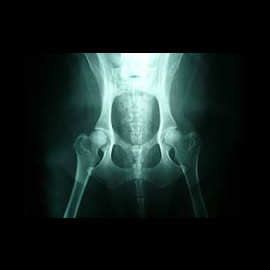

Hip Dysplasia

healthy_hips

X-ray of healthy hip joints.

Large breed dogs, particularly German Shepherds, are susceptible to Canine Hip Dysplasia.